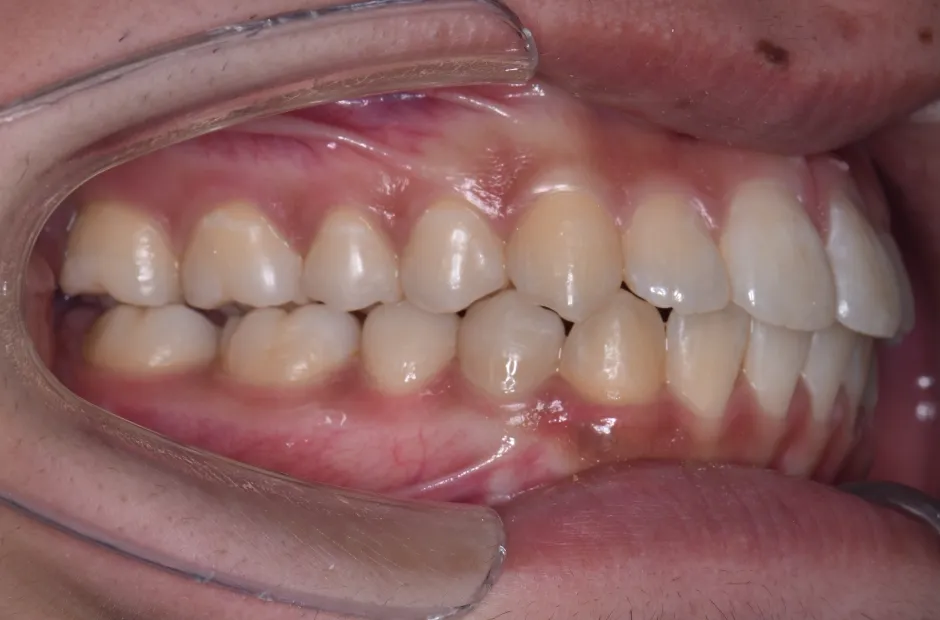

| 診断名・主訴 | 下顎前突、叢生 |

|---|---|

| 年齢・性別 | 23歳・女性 |

| 治療期間・回数 | 3年 |

| 治療に用いた主な装置 | 上顎5,5 下顎4,4 |

| 抜歯部位 | 舌側矯正 |

| 治療費 | 100万円(税抜) |

| リスク・副作用 | 装置による違和感・疼痛・歯肉退縮・歯根吸収・虫歯のリスクなど |

治療前

治療後